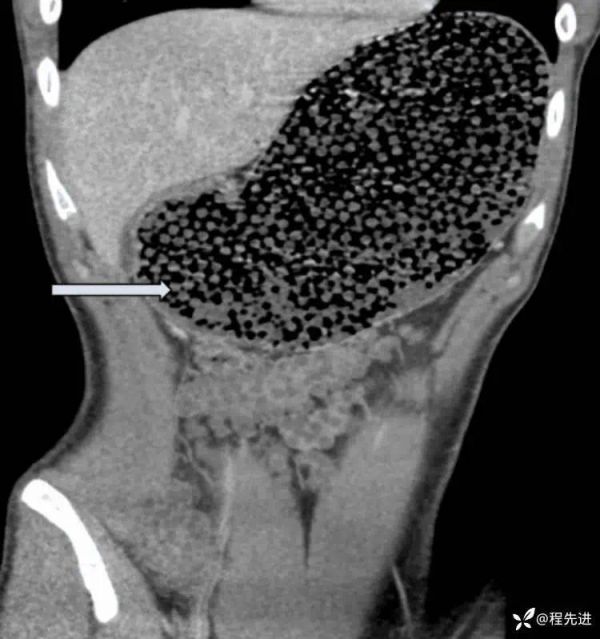

患者男,19 岁,突然「恶心、呕吐、腹痛」急诊入院。

CT 影像显示如下:

看到影像后,接诊医生倒吸一口冷气!胃内密密麻麻被填满了,男子究竟是吃了什么?

胃极度扩张,圆形颗粒状,数量大,和空气混杂,形态规则。

首先,这个东西不易消化;其次,不溶于水和酸;一次性吞服这么多,口感应该还得满足不那么难以下咽,寄生虫感染也不太可能,胃酸环境很难有寄生虫存活。上几楼说的珍珠奶茶已经被排除。